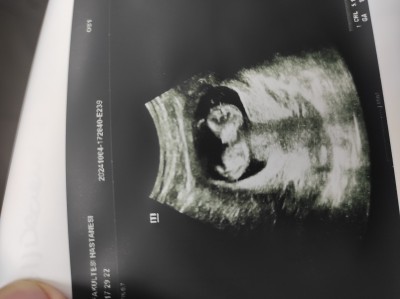

12 haftalık USG de anlayan var mı?

image

Gebelik haftası 12